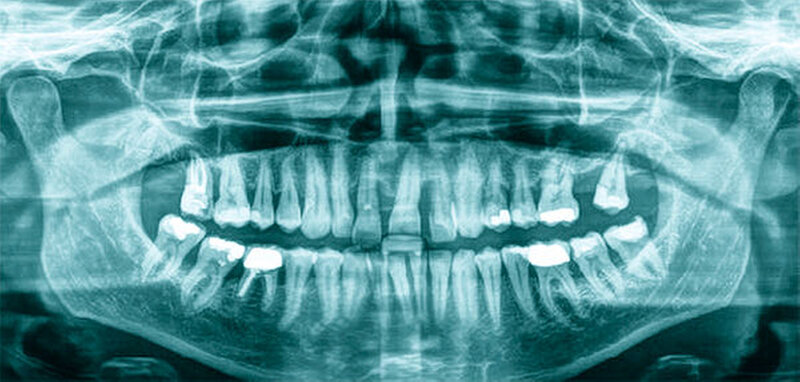

Röntgenologisch stellte sich im Orthopantomogramm der bereits intraoral ersichtliche horizontale und vertikale Knochenabbau mit Attachmentverlust an einzelnen Zähnen dar. Die Erhaltungswürdigkeit einzelner Zähne war aufgrund des starken Knochenverlustes beziehungsweise der Beeinträchtigung des Halteapparates als kritisch zu beurteilen.

Zudem wurde die Diagnose einer Parodontitis gestellt, die eine Rücküberweisung an den Hauszahnarzt erforderlich machte (Abbildung 2).